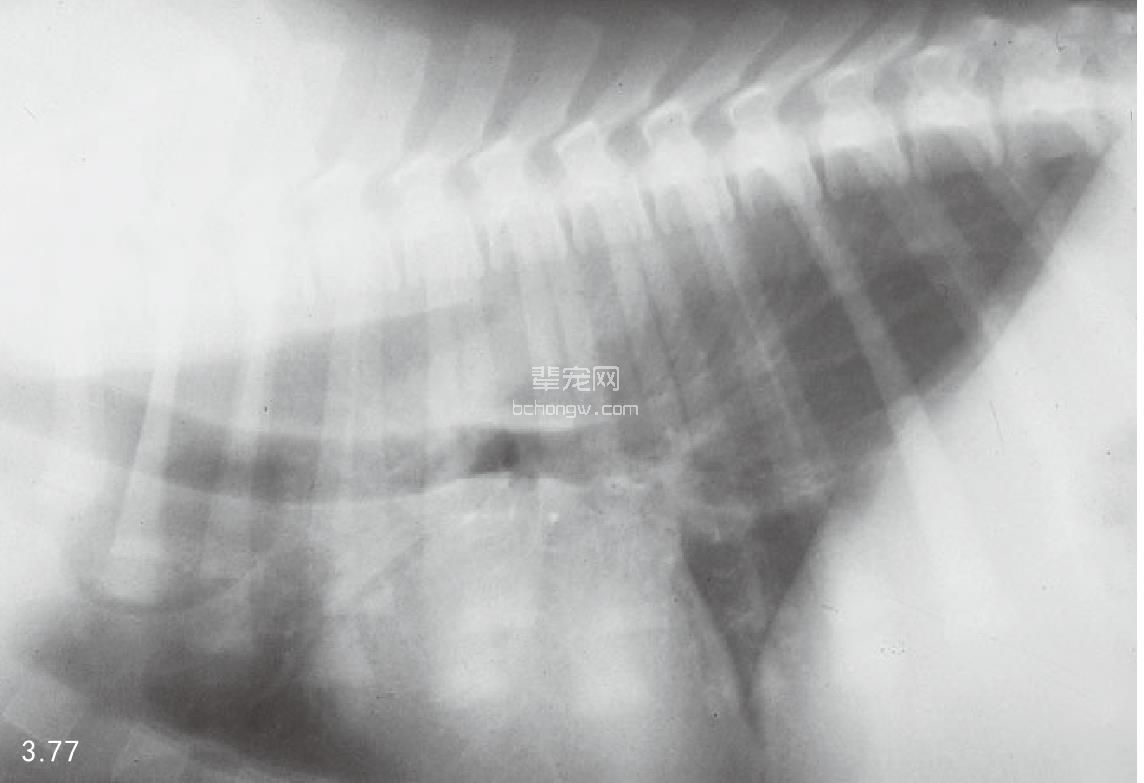

诊断 通过病史和胸腔常规X线片可以诊断 (图3.77~图3.80),但如果需要确定特殊的病 因,则需要进行额外的试验(表3.7)。如果不能 确诊可以做食管X线片和食管镜试验,但通常没有 这个必要(图3.81和图3.82)。德国牧羊犬、大丹 犬、爱尔兰赛特犬、小型雪纳瑞犬和硬毛 易患 先天性巨食管症。犬胃扩张-扭转综合征时,也 可能暂时性继发巨食管症。

图3.77 16周龄德国牧羊犬具有“玩耍时发生呕吐”史,胸腔X线检查发现为巨食管症。

图3.78和图3.79 在图3.77中所述幼犬的食道造影X线片可见食管的巨大扩张。